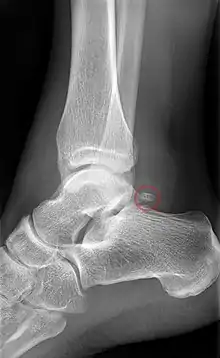

Accessory navicular

An accessory navicular bone, also called os tibiale externum, occasionally develops in front of the ankle towards the inside of the foot. This bone may be present in approximately 2–21% of the general population and is usually asymptomatic.[18][19][20] When it is symptomatic, surgery may be necessary.

The Geist classification divides the accessory navicular bones into three types.[20]

- Type 1: An os tibiale externum is a 2–3 mm sesamoid bone in the distal posterior tibialis tendon. Usually asymptomatic.

- Type 2: Triangular or heart-shaped ossicle measuring up to 12 mm, which represents a secondary ossification center connected to the navicular tuberosity by a 1–2 mm layer of fibrocartilage or hyaline cartilage. Portions of the posterior tibialis tendon sometimes insert onto the accessory ossicle, which can cause dysfunction, and therefore, symptoms.

- Type 3: A cornuate navicular bone represents an enlarged navicular tuberosity, which may represent a fused Type 2 accessory bone. Occasionally symptomatic due to bunion formation.